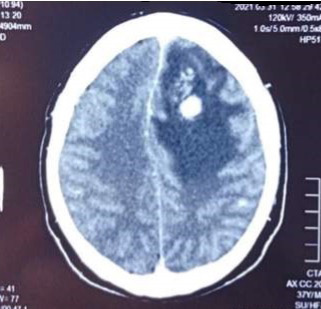

A su ingreso se le realizó al paciente una resonancia magnética cerebral (RMN) con contraste, donde se evidenció una lesión hipointensa a nivel frontal izquierdo con áreas hiperintensas en su interior que capta contraste en anillo y que se asocia a un extenso edema vasogénico (figura 1).